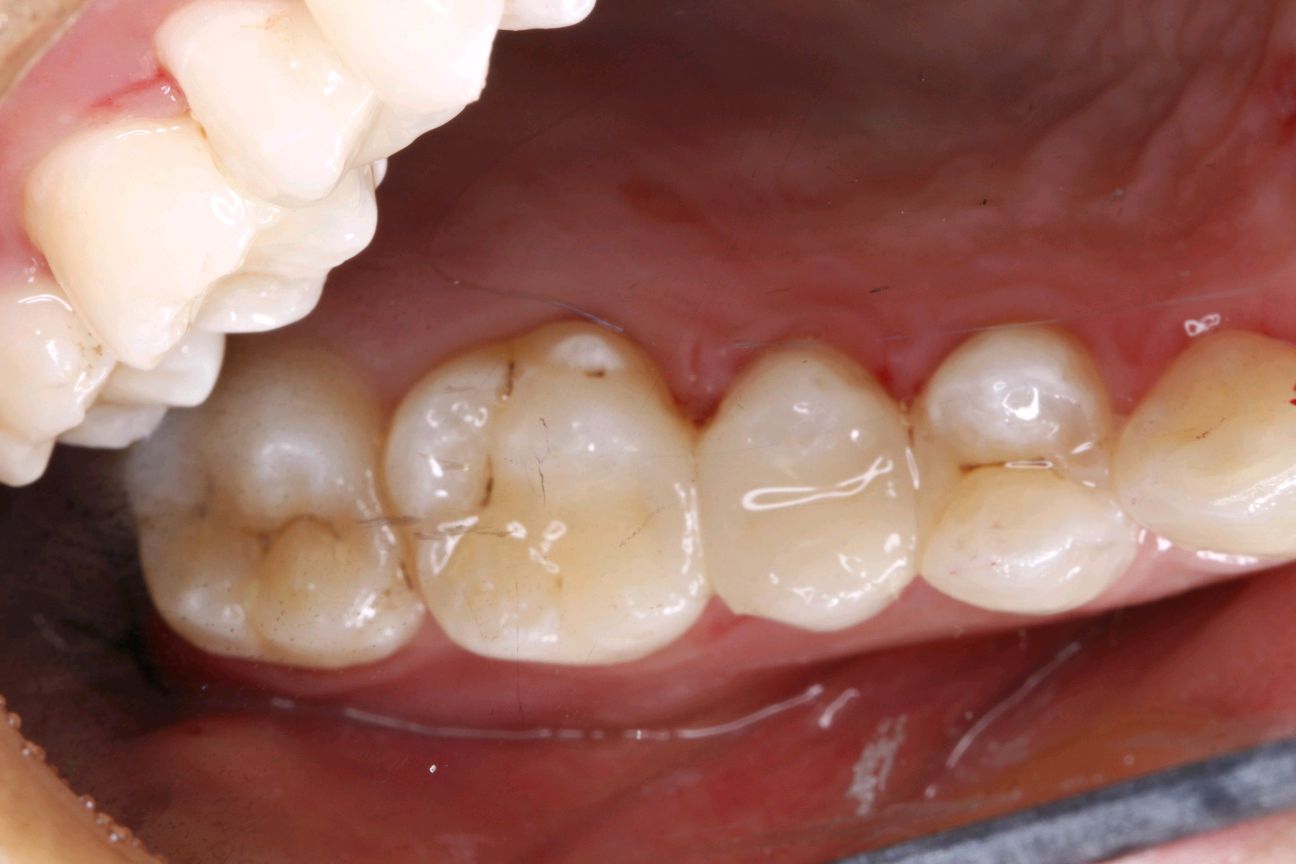

患者女,三十岁,15邻颌面大面积充填物,邻接过紧,食物嵌塞,探(+-),叩(-),冷测试正常,余无不适。很多人牙体缺损面积较大,补牙后很会出现脱落的现象,还有的让选择简单的修复模式补牙,但大量的临床研究显示,牙科树脂充填材料会产生聚合收缩(树脂材料老化),形成微渗漏,引起继发龋(顺着充填材料周围,在牙齿上出现新的腐坏、变黑)。像这种面积比较大的龋齿单纯补牙的话,不耐用。这时候就可以选择嵌体修复。嵌体牙体预备量少,能够保持牙齿外形的完整,减少对牙髓的刺激。还有就是嵌体更耐磨使用寿命较长,从而减轻了患者频繁补牙的痛苦。通过 CEREC 扫描更加精准有效的提高了我们工作效率,当天即可戴牙,正常使用。